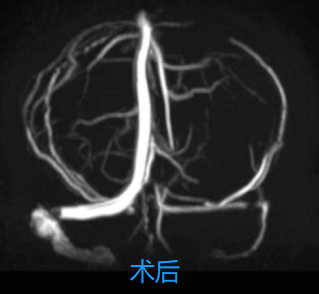

术后颅内静脉血管再通(矢状窦、横窦、乙状窦显影)。

在孙殿敬主任医师带领下,神经介入团队立即为患者行血管内治疗。脑血管造影检查证实核磁共振检查结果后,立即经股静脉逆行造影进行静脉窦血栓血管内再通治疗。经过多次支架取栓、导管抽吸,取出大量血栓,同时发现乙状窦狭窄给予球囊扩张治疗。经过5个多小时的艰苦工作,X线曝光时间约1小时,最后造影显示:上下矢状窦、横窦、乙状窦再通,颈内静脉回流通畅。术后继续给予抗凝、脱水降颅压、脑保护以及康复功能训练等治疗,经北院神经内一科全体医护人员悉心治疗与护理,患者病情逐渐好转,目前已康复出院。